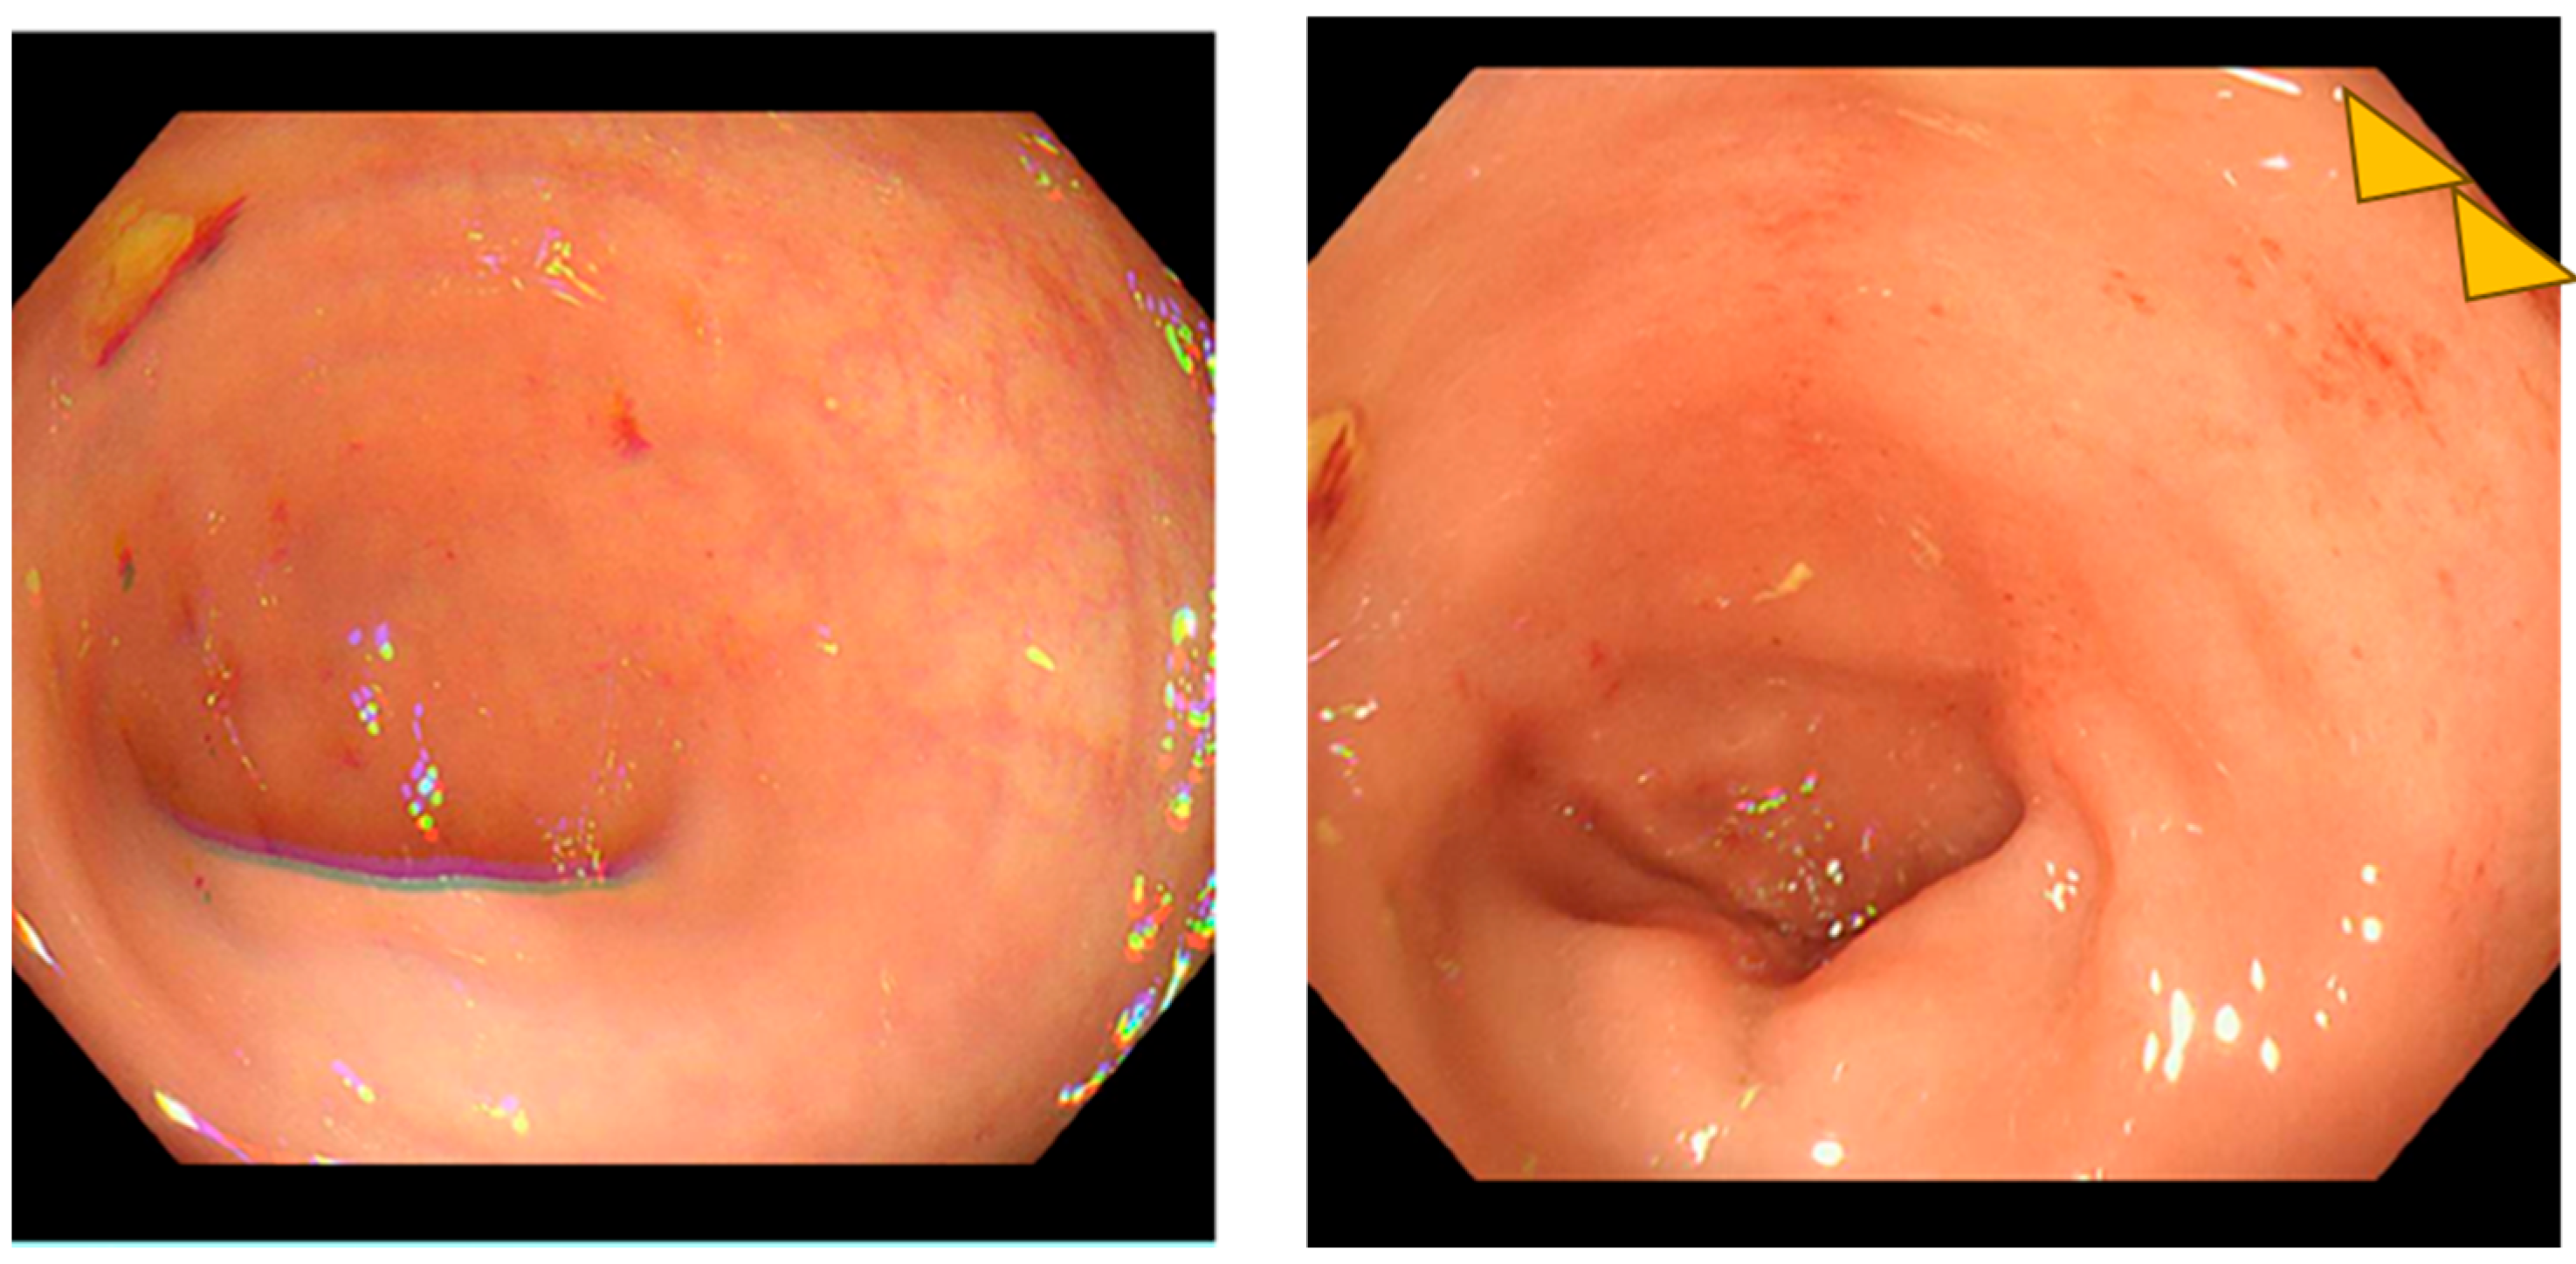

Conservative management was initiated with bowel rest, loperamide, and probiotic supplementation. The patient showed partial improvement with diarrhea frequency decreasing to 5 episodes per day by day 18. Lower gastrointestinal endoscopy was performed on day 18, revealing increased vascular permeability and mild erosions in the colon (Figure 3). Histological examination of colonic biopsies demonstrated a markedly thickened subepithelial collagen band measuring 23 μm, significantly exceeding the diagnostic threshold of 10 μm for collagenous colitis. On hematoxylin and eosin staining, eosinophilic homogeneous material was observed in the subepithelial region beneath the surface epithelium. Elastica Masson staining clearly demonstrated the extent of collagen fiber deposition as a continuous blue-stained band. The crypts maintained normal architecture without distortion or atrophy. These histopathological features, combined with the thickened subepithelial collagen band, confirmed the diagnosis of collagenous colitis (Figure 4). Lymphocyte infiltration was scarcely observed in the surface epithelium.

This case represents a rare instance of paclitaxel-induced collagenous colitis in a male breast cancer patient. The diagnosis was established through the characteristic clinical presentation of severe watery diarrhea, typical histological findings including a thickened subepithelial collagen band measuring 23 μm, and the temporal relationship with paclitaxel administration.

Collagenous colitis is characterized by a thickened subepithelial collagen band of 10 μm or greater [1,2]. Our patient’s collagen band thickness of 23 μm clearly exceeded this diagnostic criterion. The normal subepithelial collagen layer is approximately 3 μm in thickness [9].

Figure 4. Histopathological findings confirming collagenous colitis (×400): (a) Hematoxylin and eosin staining; (b) Elastica Masson staining.